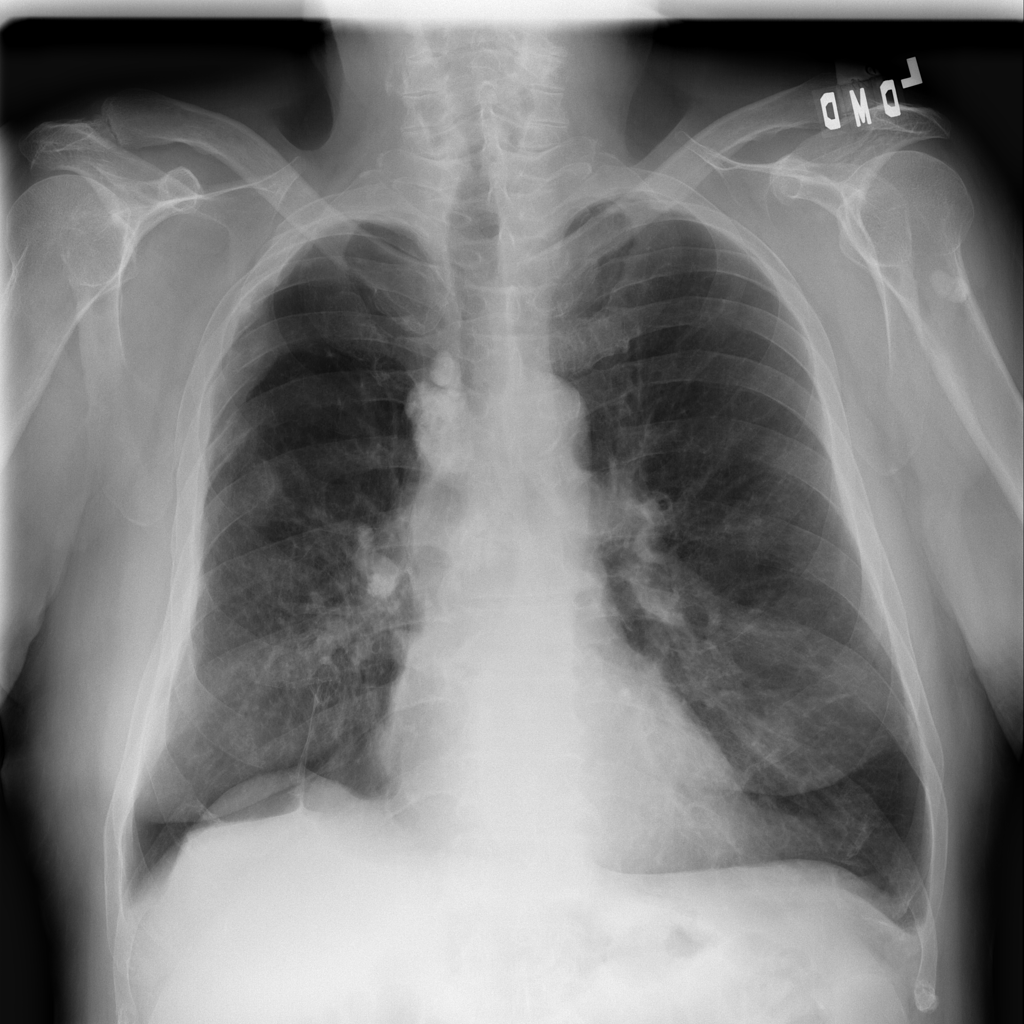

PAT-E828 · IMG-005Edema

PAT-E828 · IMG-005

AP